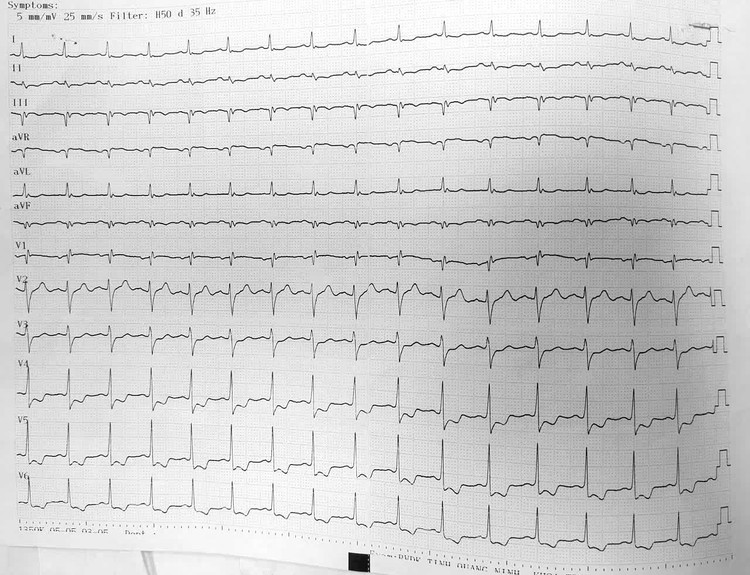

Nhịp tim bất thường trên điện tâm đồ của bệnh nhân Q. sau phẫu thuật. Ảnh BV

Vài giờ sau mổ, bệnh nhân bất ngờ xuất hiện đau ngực trái lan ra vai và cánh tay, kèm vã mồ hôi, khó thở. Nhận thấy bệnh nhân có diễn biến bất thường, các bác sĩ nhanh chóng hội chẩn chuyên khoa Tim mạch, kết quả điện tâm đồ cho thấy bệnh nhân nhồi máu cơ tim cấp thành dưới sau mổ nội soi cắt túi mật - loét hành tá tràng đang liền sẹo.